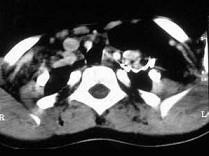

问题 女,17岁,发现左侧颈部包块半年余,PE:病灶质软,境界不清,无压痛,CT如图所示,应诊断为 ( )

选项 A、颈部淋巴管瘤 B、颈部陈旧性血肿 C、颈部畸胎瘤 D、颈部错构瘤 E、颈部脂肪瘤

答案 E